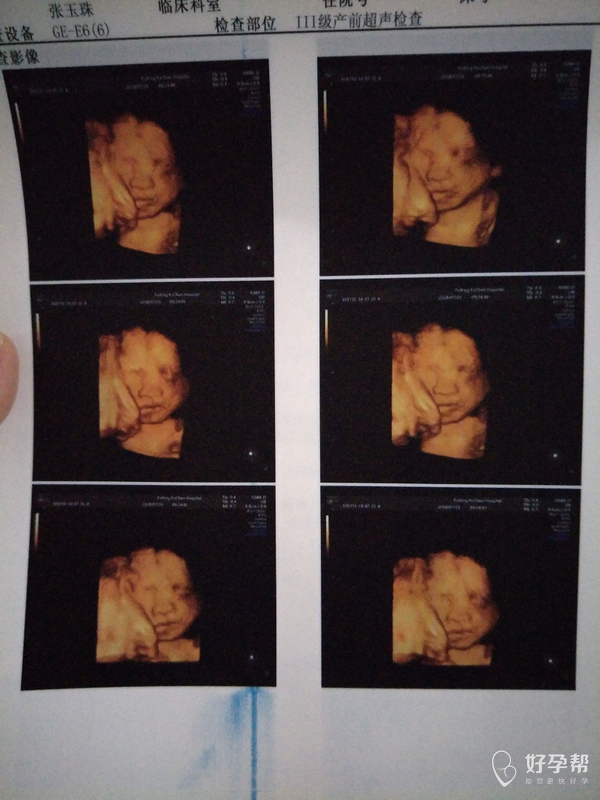

麻烦医生帮忙看看到底怎么回事